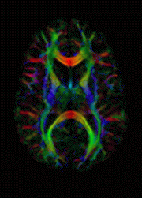

تصوير رنين مغناطيسي إنگليزية: Magnetic resonance imaging (MRI) هي وسيلة تصوير طبي لتوضيح التغييرات الباثولوجية في الأنسجة الحية و للرنين المغناطيسي أستخدمات غير طبية ومن الناحية الفيزيائية فهي تعتمد على ما يسمى بالرنين المغناطيسي النووي RMN . يعتبر التصوير بالرنين المغناطيسي من الفحوص المكلفة وغير متوفرة بشكل دائم في كثير من المستشفيات، وهناك صعوبات عند عمل هذا النوع من الأشعة عند المرضى الذين يخافون من الأماكن المغلقة أو المرضى الذين يشتكون من البدانة المفرطة.

يتكون الجهاز من مغناطيس كهربائي لولبي ضخم للقيام بتشكيل مجال مغناطيسي حول المريض. هذا المجال يجعل ذرات الهايدروجين تتمغنط وتتجه جميعها إلى جزئها المغناطيسي الشمالي فتتوحد بإتجاه واحد. بعد ذالك يعرض الجسم لأشعة مذياعية تؤدي إلى زيادة طاقة هذه الذرات ولذالك سوف تغير إتجاهها بدرجة معينة وتبعث بمقدار من الطاقة عكسي . هذه الطاقة العكسية تستقبل من الجهاز وتحسب وتتكون على شكل صورة هذه الصورة توضح شدة كثافة الهيدروجين في كل منطقة من مناطق الجسم. عن طريق هذه الصورة يتمكن الأطباء اكتشاف الكثير من الأمراض.

Diffusion MRI